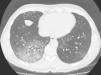

The patient is a 53-year-old man referred to our pulmonology consultation due to symptoms evolving over 5 months of cough with difficult expectoration that is sometimes hemoptoic and progressive moderate-exertion dyspnea. He had quit smoking 9 months before, with an accumulated consumption of 15 pack-years, with no reports of other toxic habits. He presented no previous respiratory pathology or occupational exposure to inhaled irritants (occupation: building engineer). The only pathological history was that 8 months before he had been diagnosed with mild high blood pressure, with no target organ injury, and had initiated treatment with eprosartan at a dosage of 600mg every 12h. Upon physical exploration, the subject was eupneic, with 16 Vf, transcutaneous oxygen saturation 98%, blood pressure 133/82mmHg, normal cardiac auscultation and lung auscultation with crackles in the lower half of the right hemithorax. Chest radiography presented small bilateral densities and chest CT showed a ground-glass pattern in the posterior basal segments of the right lower lobe and patchy areas in the left lower lobe (Fig. 1). Hemogram was normal, while biochemistry showed LDH 515U/l. Autoimmune studies with rheumatoid factor, ANA and ANCA were negative. Bronchoscopy showed no alterations; bacterial and mycobacterial cultures from bronchial suctioning were negative and bronchial cytology was normal. Transbronchial biopsy confirmed the diagnosis of interstitial pneumonitis that was predominantly lymphocytic, in the absence of vasculitis, granulomas, eosinophils and with limited fibrosis of the interstitium. Spirometry was normal, but the lung diffusion with helium (DLCO) was 41%. We considered the possibility that the interstitial lung disease was caused by the blood pressure medication that the patient was taking, so this drug was withdrawn. Twenty days later, the patient had experienced significant clinical improvements: the cough and hemoptoic sputum had stopped and the dyspnea had improved. Two months after the medication had been withdrawn, the patient was asymptomatic, and a follow-up thoracic CT showed a decrease in the interstitial pattern with changes that were limited only to the lingula; DLCO was 70%. A follow-up CT done 6 months later showed complete resolution of the interstitial alteration, and DLCO was normal. Two years after the withdrawal of the drug, the patient continues to have no clinical, functional or radiological alterations.